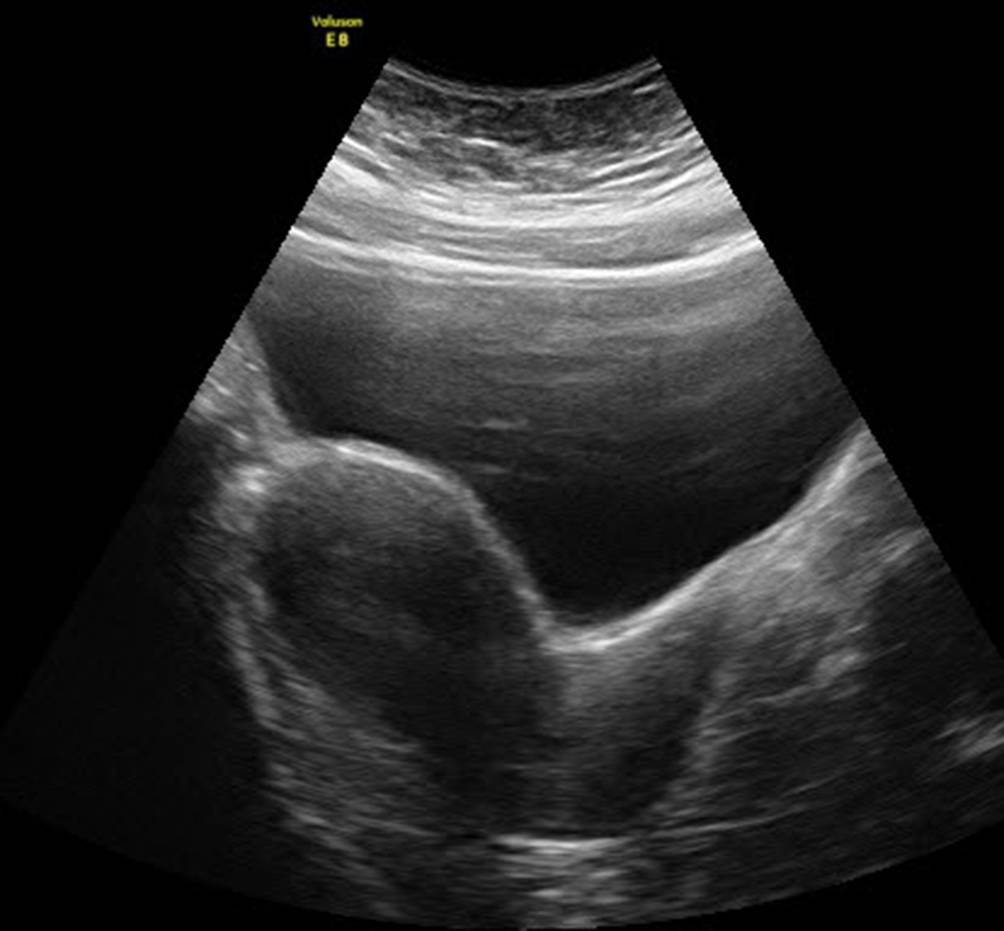

Abb. 9

Endometriosezyste von abdominal mit homogener „ground glass appearance“